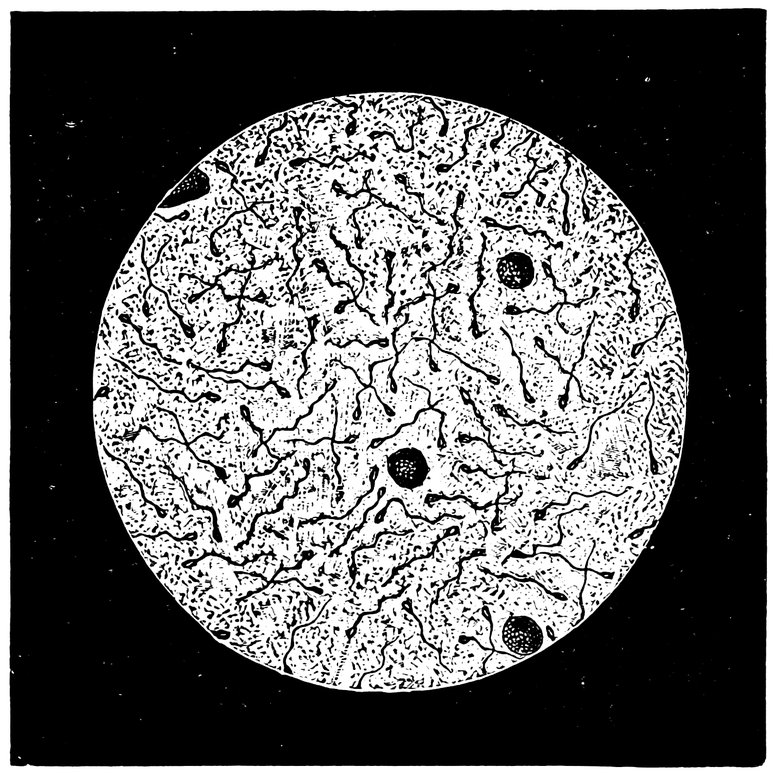

| xi82. | Mucus from the Cervical Canal, taken one hour after sexual intercourse, from a woman suffering from chronic endometritis. Among the epithelial cells, pus cells, and finely granular masses, we see a few motionless, dead spermatozoa | 531 |